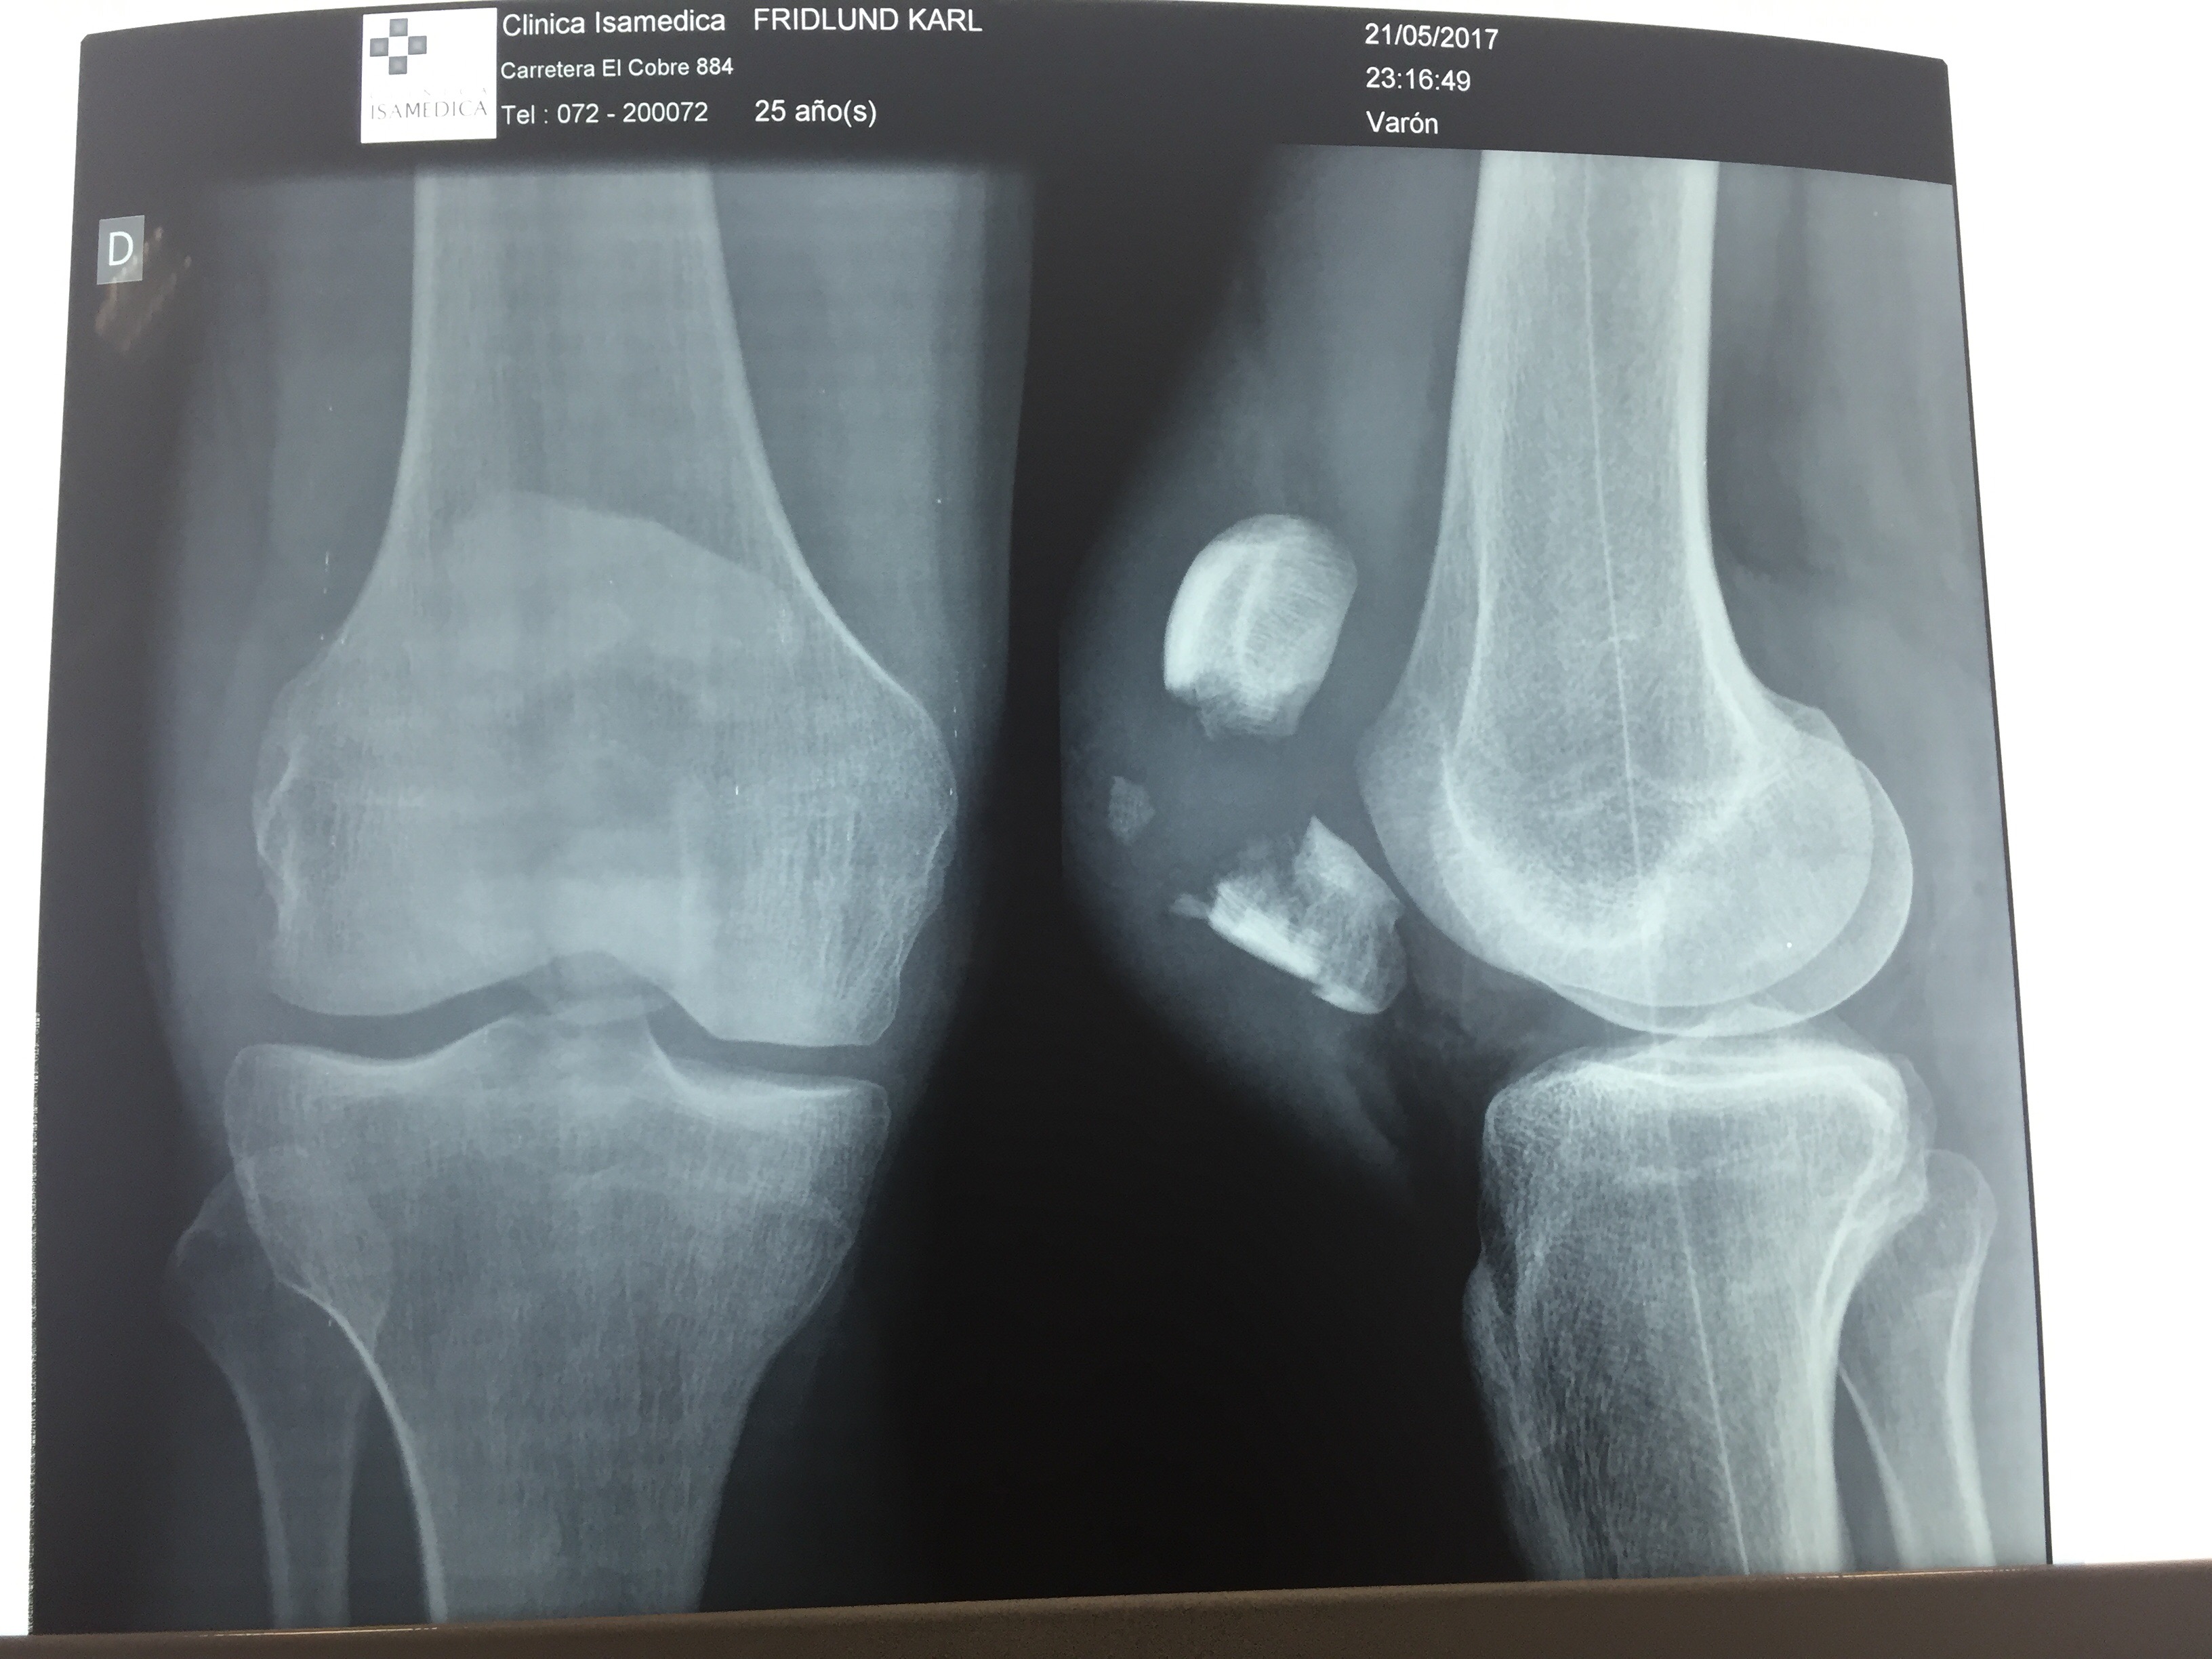

Även om jag kände att något var riktigt knasigt direkt när jag föll hade jag ändå hoppet uppe under röntgen att inget skulle vara skadat, att luxation skulle vara diagnosen och att det därför skulle gå att rätta till knäskålen så att den hamnade på rätt plats igen. Röntgenplåten talade dock sitt tydliga språk; Horisontell patellafraktur, frakturerad i huvudsakligen två delar, men med en undre del som krossats aningen mer.

Det förklarade varför jag låg där på båren och inte kunde röra benet. Förutom att givetvis smärtan var olidlig vid förflyttning fanns det inte längre någon kontakt mellan lårets muskler och smalbenet som möjliggjorde flexion. Detta är också anledningen varför en sådan här fraktur inte går att lösa på något annat sätt än med en akut operation.